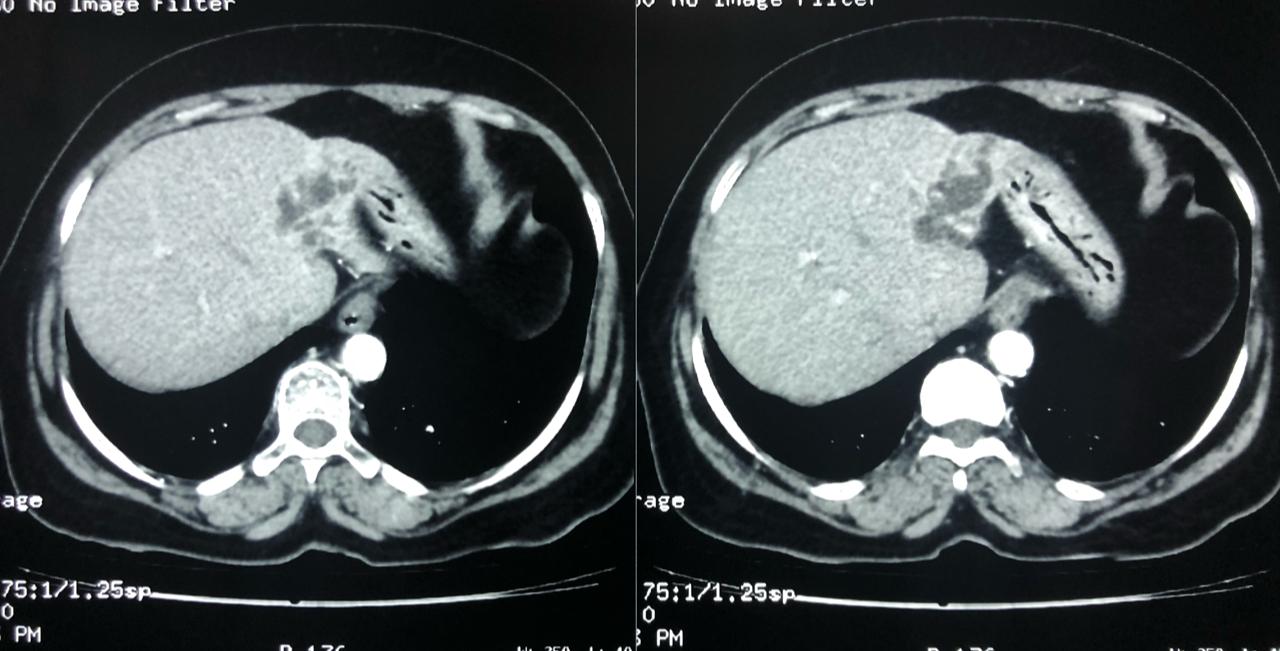

With chemotherapy improved survival with quality of life for Stage 4 cancer patient

Interesting Images March 2019 : Patient came with an early stage carcinoma rectum, underwent Hemicolectomy surgery then lost to follow-up. Later after 9 month patients presented to us with Stage 4 disease (Carcinoma colon with Liver secondaries). Then we started her on treatment with Chemotherapy along with Monoclonal antibodies with six cycle of above said treatment patient achieved near complete remission. We could achieve very good results with chemotherapy even in patients with Stage 4 disease (Carcinoma colon with Liver secondaries).